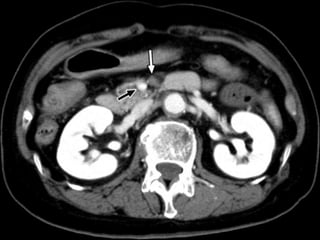

Specific CT signs

 Thromboembolism in the mesenteric

vessels

 Intramural gas

 Portal vein gas

Paper thin bowel wall

White attenuation Grey attenuation

Water target sign Pneumatosis intestinalis